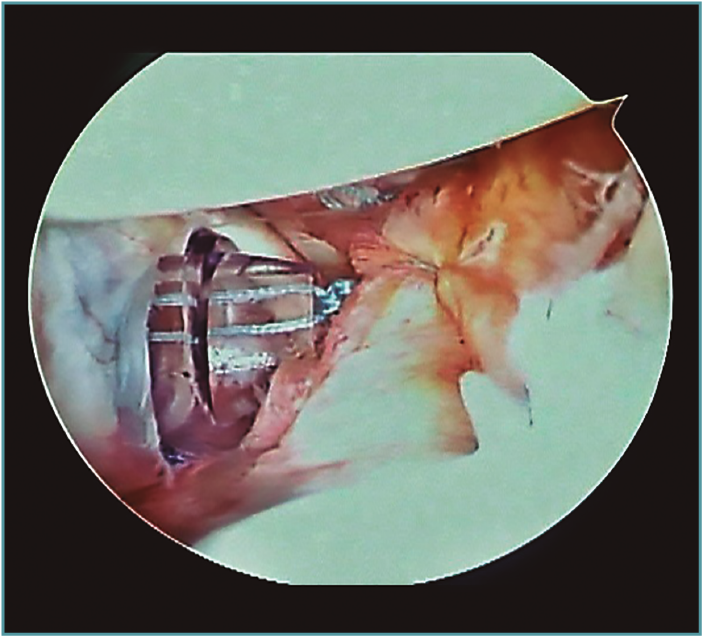

A excepción de los pacientes con significativos déficit óseos o recidivas con una mala calidad de tejido capsular, realizamos una técnica de reparación artroscópica. Operamos siempre con el paciente en decúbito lateral, con anestesia regional y general. Utilizamos siempre 4 portales instrumentales y un portal superior visual de exploración. Comenzamos nuestras cirugías con un portal de visión posterosuperior y un portal anterior de trabajo. Dependiendo de los hallazgos, realizamos las plicaturas capsulares que sean necesarias. En repetidas oportunidades encontramos hiatos intracapsulares, como por ejemplo entre el ligamento glenohumeral medio y superior, o laxitudes capsulares centrales, tratando los mismos con suturas de superior a inferior para generar una plicatura similar al capsular shift, incluso aumentando el espesor capsular (Figura 3). Luego de reparar estos defectos capsulares, seguimos nuestras plicaturas desde posterior, a través de un portal posteroinferior accesorio, colocando un anclaje con doble sutura, realizando la reparación y/o plicatura del haz posterior del ligamento glenohumeral inferior y achicando el receso inferior agresivamente siempre con anclajes de doble sutura (Figuras 4 y 5). Luego pasamos a un portal superior de visualización, dedicamos el tiempo necesario a liberar todo el labrum anteroinferior, despegando la cápsula anterior y el labrum del subescapular para movilizar e incluso acortar la cápsula, en ocasiones resecando parte de la misma para mejorar la plicatura; siempre utilizamos una sutura de tracción anterosuperior por fuera de la cánula para traccionar el tejido. Para poder llegar lo más cercano a hora 6, el primer anclaje anterior lo colocamos por un nuevo portal percutáneo transubescapular, utilizando arpones doble sutura, usando el primer par de suturas para llevar la cápsula y el labrum hacia la glena realizando sobre esta una sutura doble de tipo colchonero para mejorar la aposición capsular (Figura 6). Luego colocamos en la mayoría de los casos 2 anclajes más para terminar la reparación, en general 4 arpones. De haber un intervalo de rotadores amplio, no vacilamos en cerrarlo con suturas (Vídeo anexo).

Figura 6. Hombro izquierdo. Se visualiza portal transsubescapular para llegar a hora 6.